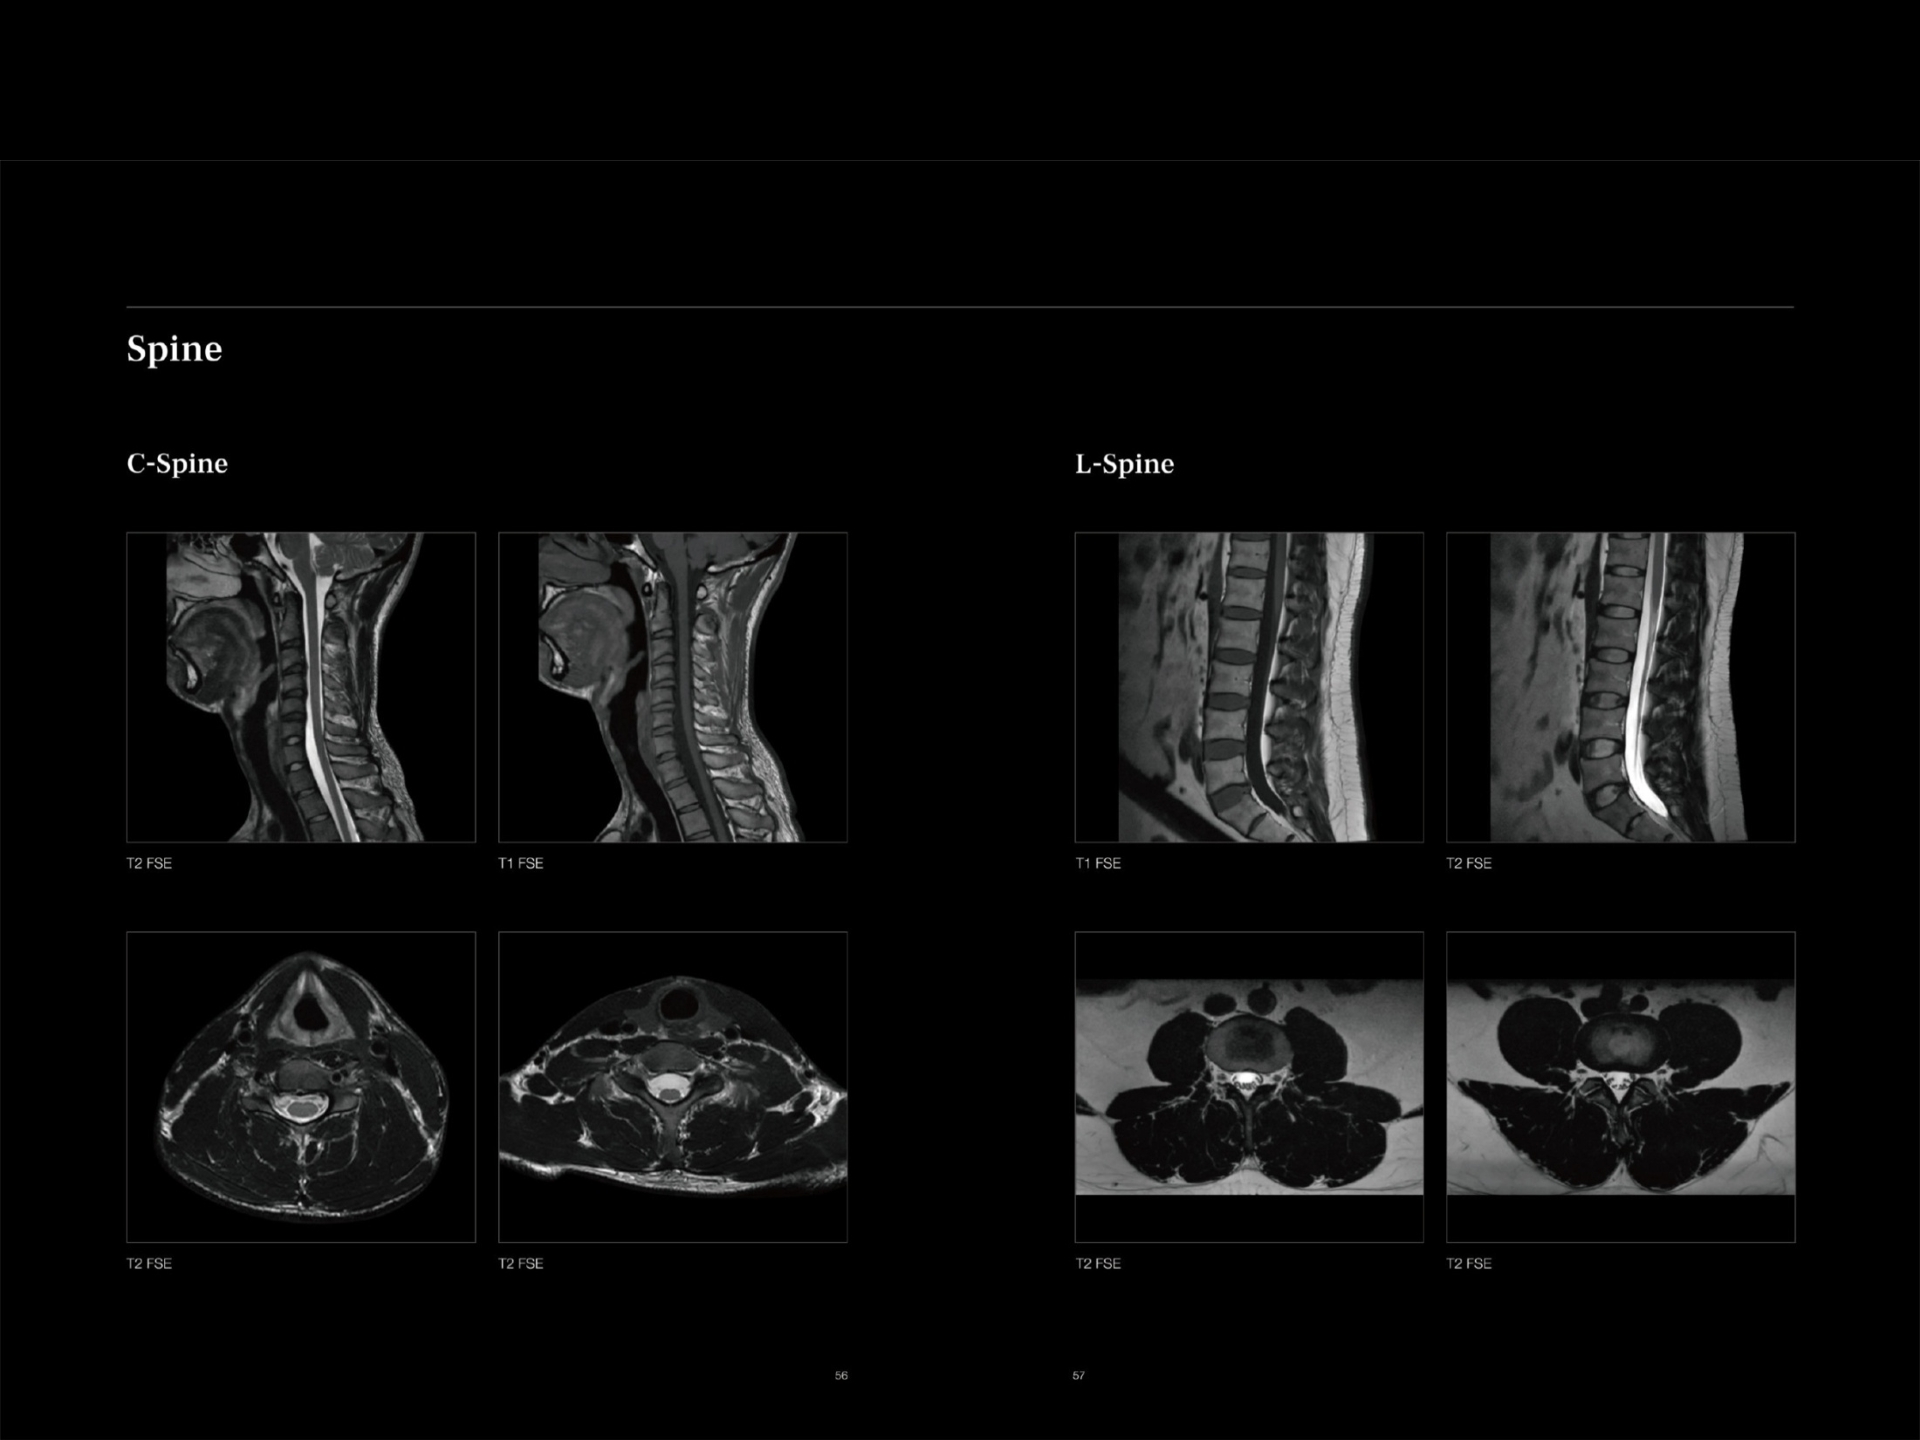

Machine has 24 dedicated Superflex body coils designed for comfort and coverage for whole body MRI and special infant coil.